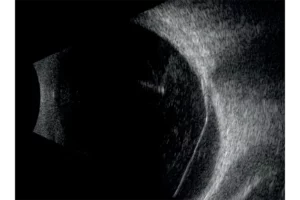

Verlengde scherptediepte van 70%

De ringtechnologie verdubbelt praktisch de scherptediepte. De 20 MHz-ringvormige sonde heeft een verlengde scherptediepte van 70%, waardoor het mogelijk is om pathologieën van het glasvocht, het netvlies en verder tegelijkertijd te observeren zonder concessies te doen aan de beeldresolutie.

- Verhoogde scherptediepte waardoor het gehele oog zichtbaar is.

- Hoge resolutie die het mogelijk maakt om van het voorste gedeelte van het glasvocht tot aan de wand te zien.